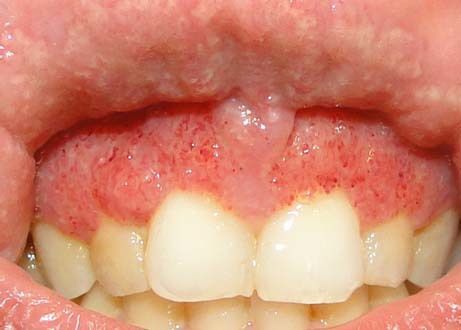

Treatment for Pyostomatitis vegetans

Management of pyostomatitis vegetans consists mainly of immunosuppression using topical or systemic corticosteroids with medical and/or surgical treatment of any underlying inflammatory bowel disease.